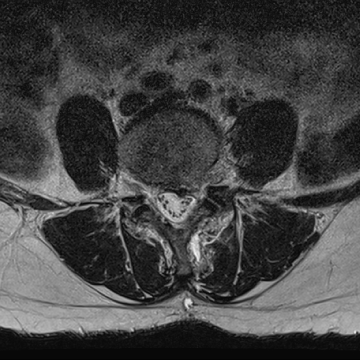

허리 디스크 수술 전·후

2021.10.19

2023.01.09